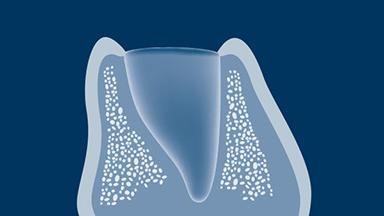

The alveolar process of the jaw develops along with the eruption of teeth, ongoing root formation, and subsequent growth.

The alveolar bone, periodontal ligament, cementum, and tooth constitute a developmental unit, as they form together.

The dimension of the alveolar process differs significantly among the various regions of the jaw, with the tooth type correlating to the size of the alveolar process.

When a tooth is removed, the developmental unit is altered, and the alveolar process resorbs.